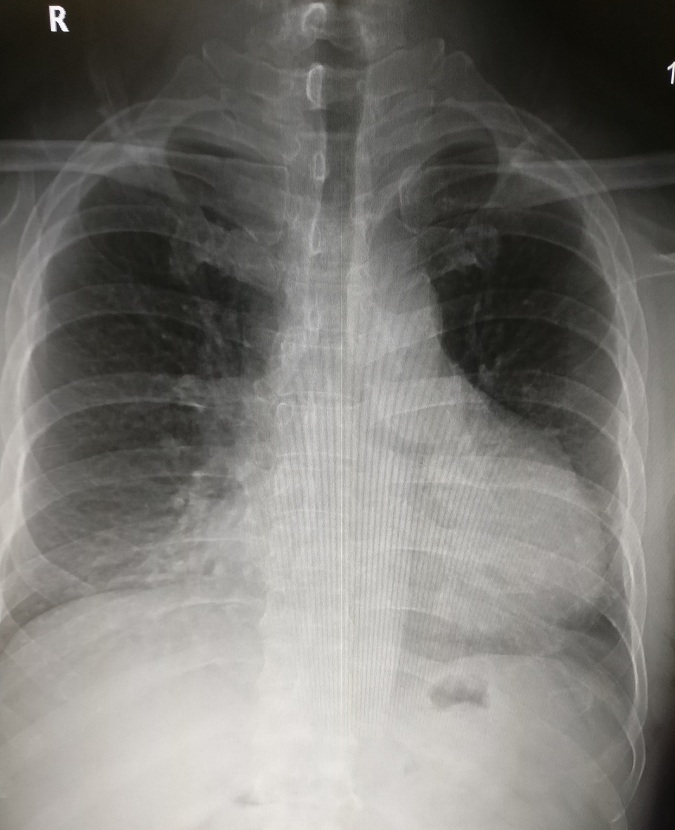

2.右心室增大

常见于心脏瓣膜病二尖瓣狭窄、肺源性心脏病、肺动脉狭窄、肺动脉高压、先天性心脏病如法络四联症等。见图2。

图2 正位片见左心缘向左侧膨隆,心尖上翘,主动脉结缩小